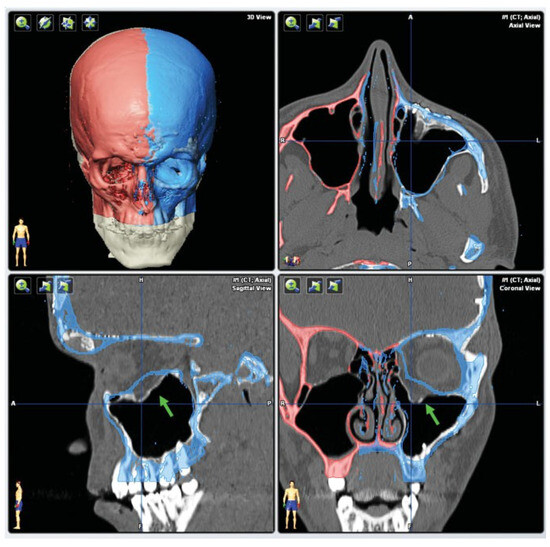

- In the case of optic canal decompression, postoperative evaluation of surgical outcome by using CT with axial and coronal thin-layer reconstructions is mandatory.